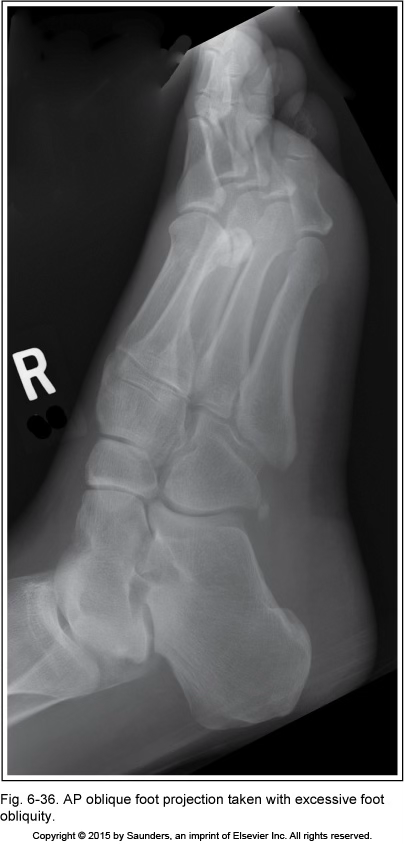

AP oblique foot

excessive foot obliquity